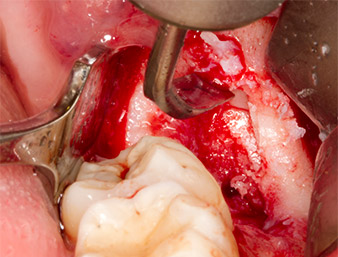

Nach Leitungs- und Lokalanästhesie wurde das Operationsfeld für einen bukkal-retromolaren Zugang weichgewebig eröffnet und dargestellt (Abb. 3).

Das Gewebe über dem Wurzelrest war nicht vollständig verknöchert und bestand zu einem großen Teil aus entzündlich verändertem Granulationsgewebe (Abb. 4).